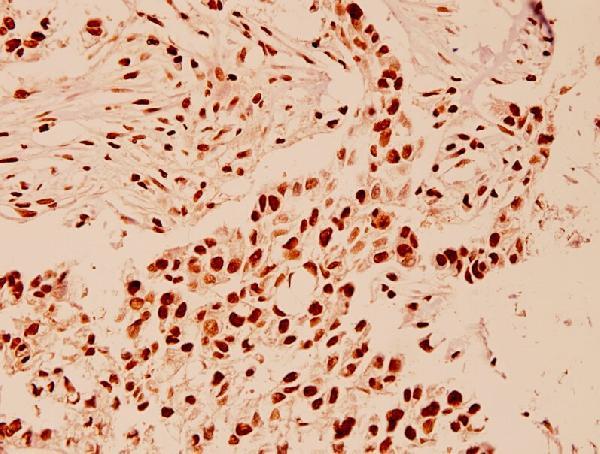

- Immunohistochemistry validation of HDAC1 using Anti-HDAC1 (E468) Antibody (A00256). Immunohistochemistry (IHC) analyzes of HDAC1 (E468) pAb in paraffin-embedded human breast carcinoma tissue at 1:100. For more protocol information of IHC